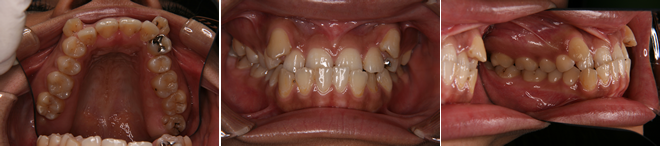

| 主訴 | 前歯のデコボコが気になる |

| 年齢・性別 | 36歳 / 女性 |

| 治療方針 | 前歯部に叢生がある切端咬合に近い軽度の反対咬合。骨格的には下顎前突。上顎の拡大により被蓋と叢生の改善を行った。 |

| 抜歯部位 | 下顎左右第3大臼歯(親知らず) |

| 使用装置 | マルチブラケット装置 |

| 治療期間 | 17か月 |

| リテーナー | 上顎インビジブル、下顎インビジブル |

| 費用 | 765,000円(税別) |